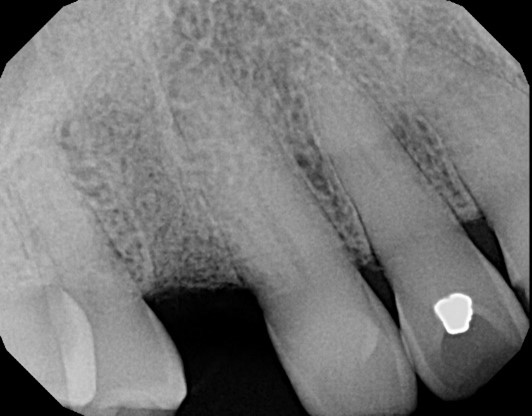

Figure Legend: A 38 y.o. white male patient presented with a chief complaint of persisting pain in the upper right area, ( tooth #5) for days. Diagnosis was endodontic lesion with a hopeless prognosis (Figure 1, 2). The tooth was extracted and Regional Acceleratory Phenomena performed (Figure 3), grafted with Allograft and Resorbable membrane (Figure 4 &5) employed for Guided Bone Regeneration (GBR) and sutured (Figure 6). Four months post Extraction and Ridge Preservation surgery (Figures 7 and 8, Implant was placed (Figure 9) to be restored after osseointegration period.